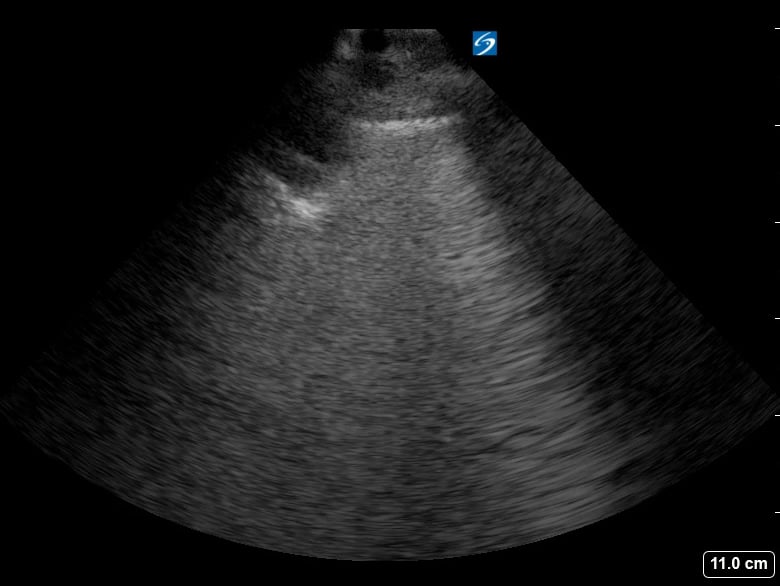

Lung consolidation in medical ultrasound refers to the solidification of lung tissue due to the accumulation of fluid, cells, or other substances, replacing the air within the alveoli. This pathological change commonly indicates conditions like pneumonia or atelectasis. On ultrasound, consolidated lung appears hyperechoic (bright) with a tissue-like echotexture, often resembling the liver (hepatization).

Identifying lung consolidation via ultrasound is crucial for rapid diagnosis and management in acute care settings. This non-invasive imaging technique allows clinicians to visualize air bronchograms (air-filled bronchi within consolidated tissue) and pleural effusions, aiding in differentiation from other lung pathologies. Ultrasound offers a portable and radiation-free alternative for bedside assessment of lung parenchyma, optimizing patient care.